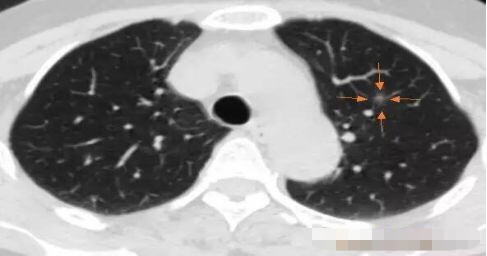

病例1 .

2014年 首次发现右肺上叶GGO,病灶直径8.3毫米, 2016年复查发现右肺上叶GGO,病灶直径12.4毫米。2年大约生长4毫米,平均1年生长2毫米。2016年手术病理结果:浸润性腺癌。

2014年 病灶8.3毫米